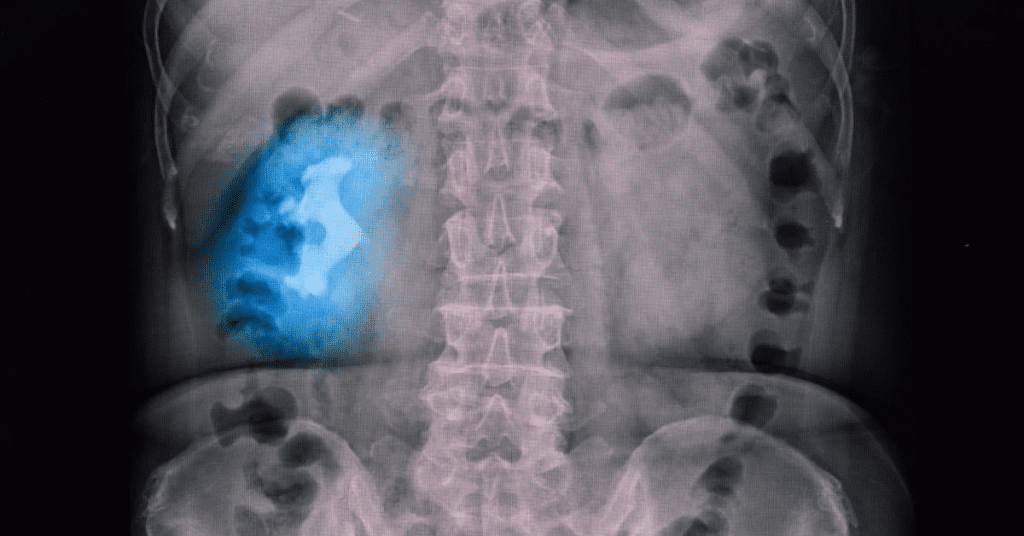

Staghorn kidney stones are one of the most challenging and potentially dangerous types of kidney stones. Known for their large, branching shape, these stones can grow to fill a significant portion of the kidney, causing pain and other serious health issues. But what exactly are staghorn stones, and how are they treated? Let’s dive into the symptoms, causes, and treatment options for these complex stones.

Staghorn kidney stones, also called staghorn calculi, are large kidney stones that take on a branched shape, often filling the renal pelvis and extending into the calyces of the kidney. These stones are typically made of struvite, a compound formed by magnesium ammonium phosphate, and are often associated with urinary tract infections (UTIs) caused by bacteria that produce the enzyme urease.

Staghorn stones are less common than other types of kidney stones and are often seen in individuals who experience recurring UTIs. They tend to be more common in women and can present serious health risks if left untreated.